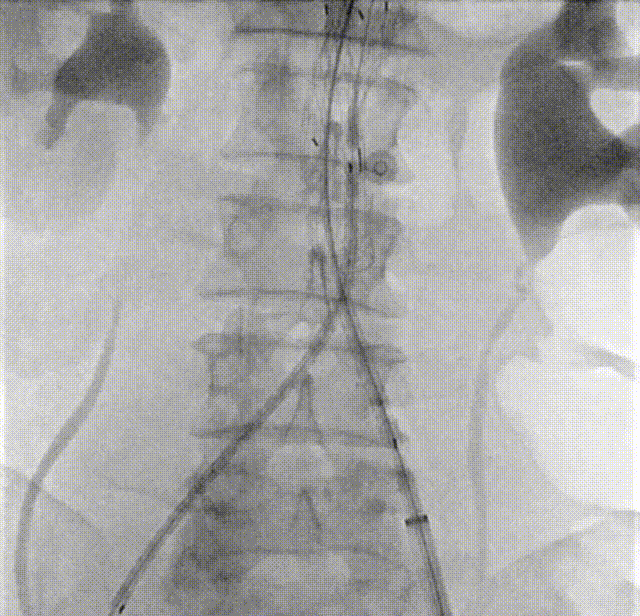

二、术前CTA详解

gore医疗怎么样「漫腹精论」髂合时宜 精益求精——双MOB球囊导管辅助腹主动脉覆膜支架急诊治疗破裂巨大髂动脉瘤_https://www.jmylbn.com_新闻资讯_第5张

gore医疗怎么样「漫腹精论」髂合时宜 精益求精——双MOB球囊导管辅助腹主动脉覆膜支架急诊治疗破裂巨大髂动脉瘤_https://www.jmylbn.com_新闻资讯_第6张

gore医疗怎么样「漫腹精论」髂合时宜 精益求精——双MOB球囊导管辅助腹主动脉覆膜支架急诊治疗破裂巨大髂动脉瘤_https://www.jmylbn.com_新闻资讯_第7张

gore医疗怎么样「漫腹精论」髂合时宜 精益求精——双MOB球囊导管辅助腹主动脉覆膜支架急诊治疗破裂巨大髂动脉瘤_https://www.jmylbn.com_新闻资讯_第8张

gore医疗怎么样「漫腹精论」髂合时宜 精益求精——双MOB球囊导管辅助腹主动脉覆膜支架急诊治疗破裂巨大髂动脉瘤_https://www.jmylbn.com_新闻资讯_第9张

gore医疗怎么样「漫腹精论」髂合时宜 精益求精——双MOB球囊导管辅助腹主动脉覆膜支架急诊治疗破裂巨大髂动脉瘤_https://www.jmylbn.com_新闻资讯_第10张

gore医疗怎么样「漫腹精论」髂合时宜 精益求精——双MOB球囊导管辅助腹主动脉覆膜支架急诊治疗破裂巨大髂动脉瘤_https://www.jmylbn.com_新闻资讯_第11张